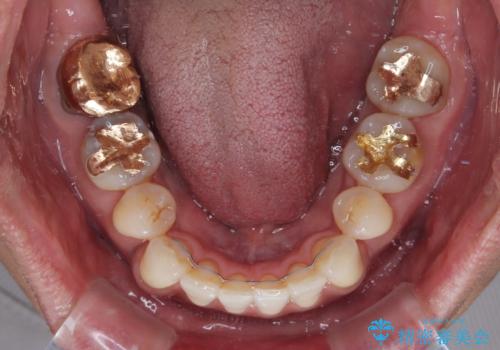

- 口元の突出感を気にして来院された患者様です。

強い咬合力と上顎前歯の傾斜により前歯が突出し、唇が閉じにくい状況であったため、上下左右の第一小臼歯4本を抜歯し、ワイヤー装置にて矯正治療を行うこととしました。

非常に咬合力が強いため、抜歯したスペースが閉じるのか不安でしたが、順調に歯が移動し、予定よりも早く治療を終えることができました。